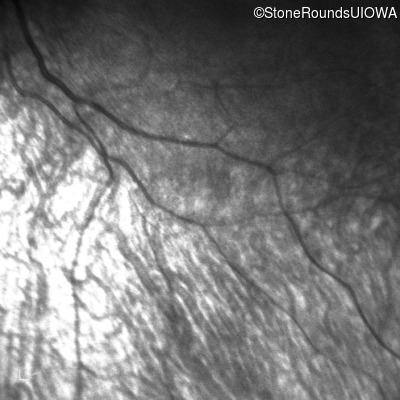

Infrared Fundus Photograph - Right -

No Light Perception

Exemplar

Infrared Fundus Photograph - Left -

Light Perception